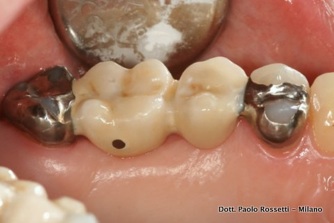

Paziente sessantenne richiede la sostituzione del primo molare superiore. Il secondo molare è già ridotto a causa di una preesistente corona protesica. L'ancoraggio sul premolare (foto dettaglio) è ottenuto rimuovendo una vecchia otturazione e producendo un piccolo box (scasso) addizionale sul dente.